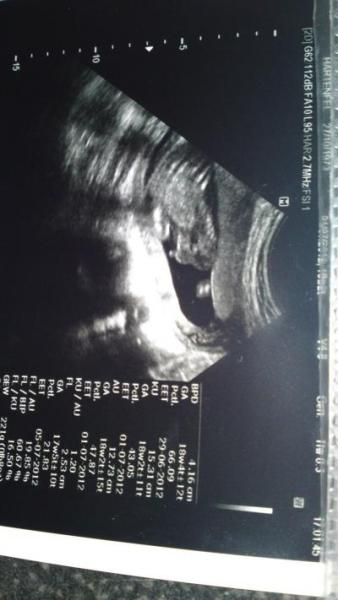

Hallo, könnt Ihr hier vielleicht was erkennen, ob Junge oder Mädchen? Viele Grüße

ohhh ich find,das ist schwer seh bar. Also ich seh da nen Schniepel,aber ob es wirklich einer ist..hmm... kann aber auch der Daumen sein...man erkennt da wirklich irgendwie gar nichts.Also keine beinchen,popo oder sont was

kann nicht erkennen, meine den po sehen zu können. stimmt das?

Also ich erkenne da den Kopf und die Ärmchen, die Hände neben den Wangen und irgendwie geht dann der Körper so nach hinten... der Po und so ist glaub ich gar nicht zu sehen, das Ganze liegt in einer anderen Ebene... Oder interpretiere ich das falsch... Du kannst ja das andere US-Bild noch mal etwas größer rein stellen, ich finde auf den anderen war nicht viel zu sehen, da dort auch das Licht gespiegelt hat... LG deine Keksi

Hallo, also ich erkenne da mittig nur diesen kleinen Knubbel (wenn das dann der Pullermann sein soll). Wie das Baby letzendlich da liegt, kann ich nicht sagen bzw. erkennen. Ärztin hat auch nichts weiter gesagt :-(